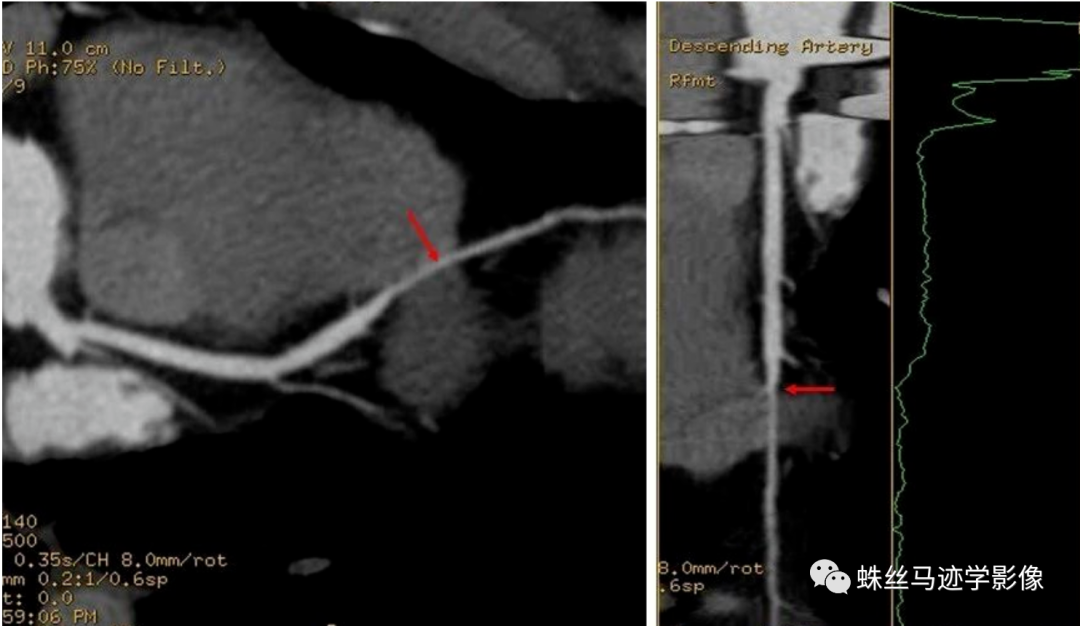

心肌桥/壁冠状动脉:冠状动脉及其分支通常走行于心包膜下方,但有时会以不同的深度在心肌纤维之间走行,然后重新出现在心脏表面,而在心肌纤维内走行的动脉被称为壁冠状动脉 mur alcoronaryartery,MCA),覆盖于冠状动脉上方的心肌称为心肌桥( myocardialbridging,MB)。